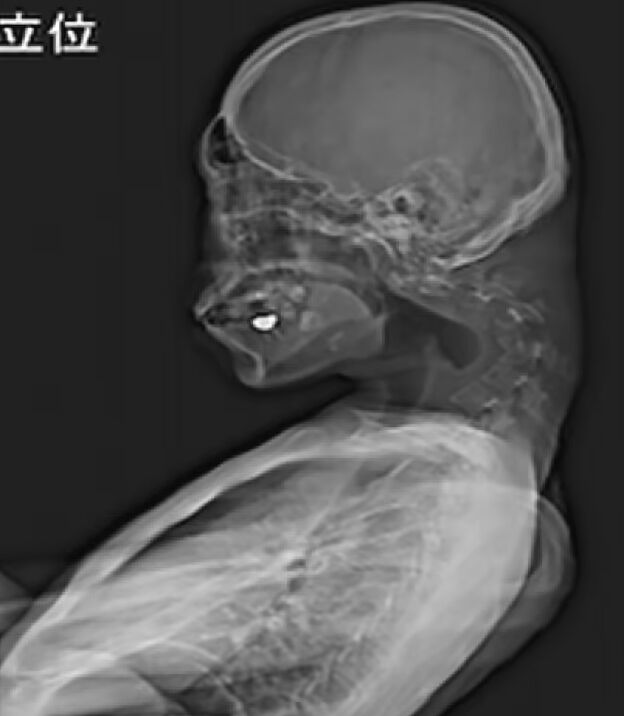

İlginç olay Japonya’da yaşandı. Bilgisayar oyunlarıyla yakından ilgilenen 25 yaşındaki genç, uzun saatler ekrana baktığı için 'düşük baş sendromu' adı verilen rahatsızlığı geçirdi. Şiddetli boyun ağrısı şikayetiyle doktora başvuran genç adam, röntgen çekilmesinin ardından şoke oldu.

Yapılan taramaların ardından konuşan doktorlar, gencin boynundaki omurların yerinden oynadığını bunun sonucunda da omurgada zamanla yara benzeri dokular oluştuğunu tespit etti. Teşhisin ardından tedavi için harekete geçen doktorlar, genç hastaya başının sabit durabilmesi için boyunluk takmayı önerseler de bu tedavi yeterli gelmeyeceği için kısa sürede sonlandı.